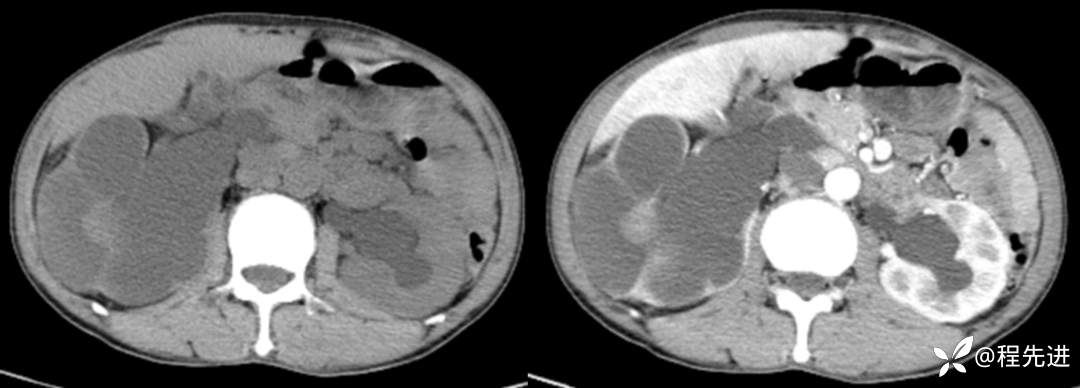

CT平扫+增强

来张特定(左平扫,中动脉期,右静脉期)

冠状位重建